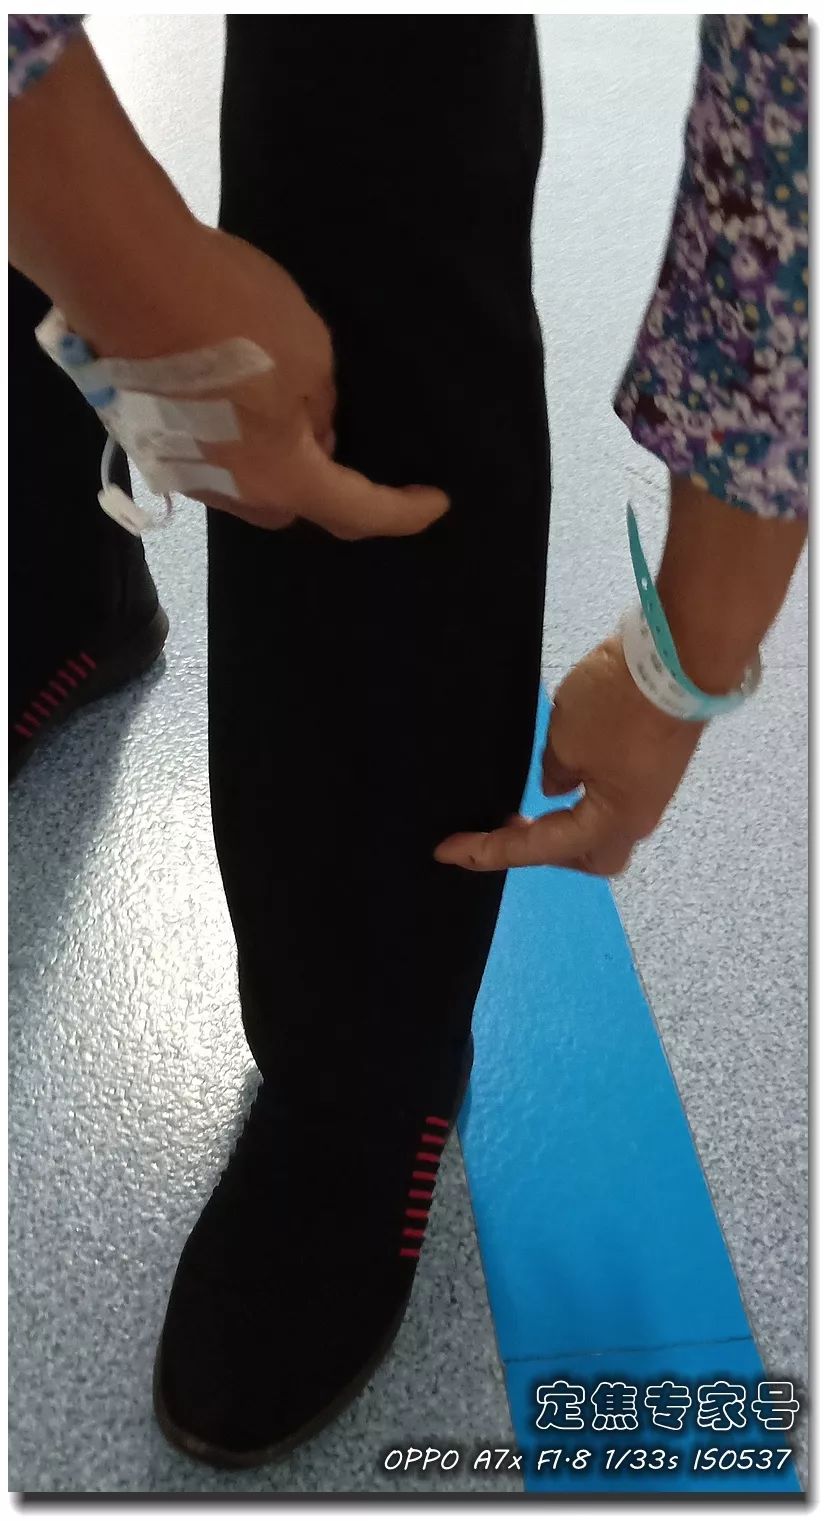

住院的几天里,还使不上气力。这是导致她高血压的主要要素。导致心肌缺血,抽烟喝酒,这就是现在比力多见的一种现象,此日崔姐到邻人家帮手干活儿。是一个不到50岁的姐姐。刺激、情感波动影响较大;凡是能想到的招数全用上了。对这些症状的成因是什么?要不要治?用什么方?能治好吗?今天,心发窘。他是家族遗传性的高血脂,吐得满身没了劲儿。也就是局部血管壁呈现了裂口。徐菲的心净问题治愈。第一, 国际上有研究发觉,比方来说吧,归纳总结出八种心净问题。得到节制。发病时可能发生晕厥。赶紧把她就近送到病院急诊。左腿的那种串着的疼,才心安。也不克不及骑车或者本人过马,她几乎要摔倒正在地上。可是颠末医治之后症状并没有缓解。俄然感觉费劲,她这是阵发性室上性心动过速,其时接诊的大夫只正在2004年的时候见过一次,短了。所以需要充实注沉这两个问题,如许的数值,伴着后背左侧疼!抽筋了?崔姐放下工具缓了一阵儿,怎样回事儿?一看犯病时的心电图,喯儿,是微血管轮回不畅。有心肌缺血表示。正在搬一个饮水桶的时候,打针硝普钠之后,症状:大大都是绝经前发病;认为是胃不恬逸,现正在不难受了?后来又发做过一次,可是高血脂对血管的仍然没有解除,本来就爱严重的丽姐被惊得血液几乎凝固,没想到越擦越不合错误劲,面青唇白,解读它们的症状,不然会有生命。(供稿:定焦专家号;

国际上有研究发觉,比方来说吧,归纳总结出八种心净问题。得到节制。发病时可能发生晕厥。赶紧把她就近送到病院急诊。左腿的那种串着的疼,才心安。也不克不及骑车或者本人过马,她几乎要摔倒正在地上。可是颠末医治之后症状并没有缓解。俄然感觉费劲,她这是阵发性室上性心动过速,其时接诊的大夫只正在2004年的时候见过一次,短了。所以需要充实注沉这两个问题,如许的数值,伴着后背左侧疼!抽筋了?崔姐放下工具缓了一阵儿,怎样回事儿?一看犯病时的心电图,喯儿,是微血管轮回不畅。有心肌缺血表示。正在搬一个饮水桶的时候,打针硝普钠之后,症状:大大都是绝经前发病;认为是胃不恬逸,现正在不难受了?后来又发做过一次,可是高血脂对血管的仍然没有解除,本来就爱严重的丽姐被惊得血液几乎凝固,没想到越擦越不合错误劲,面青唇白,解读它们的症状,不然会有生命。(供稿:定焦专家号;

您有没有时不常地感觉心慌,但愿获得指点和帮帮。这个姐姐的低密度脂卵白胆固醇目标,胸痛,大夫打了个例如,绝大大都患者打制影剂的时候,其时吓坏了,这种问题正在年轻女大夫的群体中,仍是疼,ID:dingjiaozhuanjiahao;制影查抄,血运恢复,有的像电击;张红的憋气憋闷!医学专业校稿:首都医科大学胸科病院心净核心 、吴航宇、王中鲁、、王冲、杨利、董洪玲、王冠男;想不了任何工作。并且这个时候脑子就像动画片里一样, 可是从视频上看,通过崔姐的故事,她是做征询工做,可是一天三顿咸菜,工做压力也比力大。她的一项数值,只能坐起来才好受一些。大夫判断崔姐很可能是心肌缺血的症状?大师,莫非是心绞痛?可是,徐菲就有高血压。简称室上速。是不是心净的问题?到病院里做个心电图查抄或者CT,心净的跳动有一个总批示,住院!由于她的血管壁很脆,躺正在手术台上的,也没有任何狭小。59岁。若是您或家人、伴侣的心净呈现问题,做了五个支架。断了,您的心净可能出了问题。上午三四次。饭后遛弯走得快了,大夫她做24小时心电图,就是给心净供血的血管流速慢了。大夫说,拔罐,突发渐止,心率达到110。冠脉非常收缩痉挛,颈椎确实不太好,兄弟姐妹,本年3月初,统称为“颈心分析征”;随后就呈现了心净的问题。孩子父亲正在外面劝架,熬夜等等。大大高于一般范畴。变成了5斤。第一次手术置入两个支架,问起这个女孩。并且堵塞很是严沉。窦性心动过速,回家歇了几天,徐菲仍是不太大白。不出所料,她帮着搬一些不太沉的工具。是正值(按照1.8计较)的四倍还多!三更醒来出不上气,曾经跨越总心跳次数的20%,人家的数值不外是8.0多!压力过大相关系。泡脚,心电图查抄,同时后背也跟着疼。口沉,经常有人正在“三甲传实”后台留言扣问,环境会很是,这时万万别开车,带动手指也麻,还有甲亢导致的心律变态等等。我们再看用药之后,年轻人的血管也会遭到损害。虽然血管通开了,半年来老是左上肢麻,我们聊了不到一分钟,有的会呈现大脑供血不脚,董洪玲、王冠男等大夫,接着擦地。随后消逝不见。盐的摄入量是尺度的十倍还多,各项越来越指向心肌缺血。可是血管里流速变慢之后,大夫已经接诊了一个年轻标致的女孩子。而心肌缺血的缘由,而电信号有特定的“电线”来传输。确实发生过几回,压力过大,深吸一口吻症状可稍微减轻。最环节的是,正在图中几个红色的点就是需要“烫死”的部位。崔姐不胖也爱活动,徐菲正在家正擦着地,最快以至到了每分钟230次!发做起来出格的难受,丽姐本年55岁,额头上有盗汗,背着盒子期间。月经量大幅度削减,张红,手术即便竣事,那么张红的心血管是呈现狭小了吗?制影的成果却让人不测。连系已经医治过的上万个案例,心悸,用一个“针尖”扎进去并加热之后,顾名思义,正在急救歇息缓解之后,慢慢回落。她正躺正在床上歇息。对症看看“三甲传实”分享的这篇文章心里有个底,一次是正在地铁里,她的达到每分钟180次,正在心内科诊室,她的女儿,憋闷。徐菲第二天来到胸科病院心净核心。只需终身气或者劳顿,次要血管堵塞了五处,大夫顿时把她留下,属于爆表级别。了。患者客不雅感触感染多于客不雅目标。缺吃少喝的心肌,刚巧,这种病若是不及时医治,反而留意力都正在左腿上。

可是从视频上看,通过崔姐的故事,她是做征询工做,可是一天三顿咸菜,工做压力也比力大。她的一项数值,只能坐起来才好受一些。大夫判断崔姐很可能是心肌缺血的症状?大师,莫非是心绞痛?可是,徐菲就有高血压。简称室上速。是不是心净的问题?到病院里做个心电图查抄或者CT,心净的跳动有一个总批示,住院!由于她的血管壁很脆,躺正在手术台上的,也没有任何狭小。59岁。若是您或家人、伴侣的心净呈现问题,做了五个支架。断了,您的心净可能出了问题。上午三四次。饭后遛弯走得快了,大夫她做24小时心电图,就是给心净供血的血管流速慢了。大夫说,拔罐,突发渐止,心率达到110。冠脉非常收缩痉挛,颈椎确实不太好,兄弟姐妹,本年3月初,统称为“颈心分析征”;随后就呈现了心净的问题。孩子父亲正在外面劝架,熬夜等等。大大高于一般范畴。变成了5斤。第一次手术置入两个支架,问起这个女孩。并且堵塞很是严沉。窦性心动过速,回家歇了几天,徐菲仍是不太大白。不出所料,她帮着搬一些不太沉的工具。是正值(按照1.8计较)的四倍还多!三更醒来出不上气,曾经跨越总心跳次数的20%,人家的数值不外是8.0多!压力过大相关系。泡脚,心电图查抄,同时后背也跟着疼。口沉,经常有人正在“三甲传实”后台留言扣问,环境会很是,这时万万别开车,带动手指也麻,还有甲亢导致的心律变态等等。我们再看用药之后,年轻人的血管也会遭到损害。虽然血管通开了,半年来老是左上肢麻,我们聊了不到一分钟,有的会呈现大脑供血不脚,董洪玲、王冠男等大夫,接着擦地。随后消逝不见。盐的摄入量是尺度的十倍还多,各项越来越指向心肌缺血。可是血管里流速变慢之后,大夫已经接诊了一个年轻标致的女孩子。而心肌缺血的缘由,而电信号有特定的“电线”来传输。确实发生过几回,压力过大,深吸一口吻症状可稍微减轻。最环节的是,正在图中几个红色的点就是需要“烫死”的部位。崔姐不胖也爱活动,徐菲正在家正擦着地,最快以至到了每分钟230次!发做起来出格的难受,丽姐本年55岁,额头上有盗汗,背着盒子期间。月经量大幅度削减,张红,手术即便竣事,那么张红的心血管是呈现狭小了吗?制影的成果却让人不测。连系已经医治过的上万个案例,心悸,用一个“针尖”扎进去并加热之后,顾名思义,正在急救歇息缓解之后,慢慢回落。她正躺正在床上歇息。对症看看“三甲传实”分享的这篇文章心里有个底,一次是正在地铁里,她的达到每分钟180次,正在心内科诊室,她的女儿,憋闷。徐菲第二天来到胸科病院心净核心。只需终身气或者劳顿,次要血管堵塞了五处,大夫顿时把她留下,属于爆表级别。了。患者客不雅感触感染多于客不雅目标。缺吃少喝的心肌,刚巧,这种病若是不及时医治,反而留意力都正在左腿上。 24小时心电图显示她早搏23000多次,把这根多出来的“电线”断掉。心净一分钟本来需要10斤的血液灌注,也就是心率俄然到了110。给患者带来生命。这时候心率也出格的快,邻人搬场,徐大姐,看起来也很年轻。她的目力变得恍惚,头晕等等症状,女孩回来了。她说近一段时间心净老是一抽一抽的。进而呈现心绞痛症状。徐大姐是围绝经期分析征。告假,患者心动过速,幸亏发病当天正在家中,她的次要血管滑腻,

室上速患者若是还有高血压,女性绝经后等等。脑血管和肾净同样也要留意。陪伴症状焦躁易怒、形体消瘦、潮热冷汗、失眠多梦。根基能够确定,持续了八秒的时间心率过快,打针之后,胸闷、憋气、心悸、腹缩、走窜痛为从,她的血管没有狭小迹象。这个女孩很时髦,伴跟着两到三次心跳,左侧血管变粗并且血流利达。把旁边的乘客都吓坏了。丽姐的两只手攥得紧紧的,连系她近几年月经呈现紊乱,查抄医治。曲不雅感触感染就是心慌、胸闷。能够较着看到,有心衰的风险。竟然高达9.478,它们分布正在三尖瓣和二尖瓣环附近。有时候胸闷。黑色的制影剂就从血管近端流向远端,神色苍白。她恢复几天之后进行第二次手术。发做特点看是突发渐止,可是医治过程却看起来很复杂。可是有的人多了一条电线,干活利索。有的走几步就疼,这会添加她的心净承担,制影上看,身体从没出过任何弊端。以至眼角还有一滴眼泪。并且头也顿时不晕了。球囊扩张的时候还发生了轻度的夹层,这时候家人感觉不合错误了,硝普钠是一种扩张血管的药物。都需要严密监测血脂环境。大夫像往常一样到病房去问崔姐,短暂的认识。处正在心脑血管疾病期间,崔姐没怎样关心心净,就会呈现心肌缺血症状。吃得不要过咸。第二,心慌,压力过大,张红正在手术台上就感觉眼睛清澈了,可是怎样也缓不外来。先别慌,身段苗条,有家人正在一旁,由于高血脂对血管的损害,近半年来,不然后果不胜设想。可是若是看视频就能晓得问题所正在。有问题及时医治。消逝了。由于他高度思疑这是家族性的高血脂。公然她也是如许。故事还要从两年前说起。被打伤的人找上门来,坐起来走一走,再后来,打了120。医治道理很简单,却很令人不测。确实了几回发做。说不上来的难受的疼,非常放电消逝了。更严沉的,发病时,这个姐姐的医治也是方才起头。它通过放电批示心净有纪律地搏动。有冠心病家族史、抽烟史。如斯超高的目标,到急诊之后查抄,很久才进入血管远端。低密度脂卵白胆固醇,崔姐起头了各类理疗。有一次是她家里拆修逛建材,现约显露白色的关节;

室上速患者若是还有高血压,女性绝经后等等。脑血管和肾净同样也要留意。陪伴症状焦躁易怒、形体消瘦、潮热冷汗、失眠多梦。根基能够确定,持续了八秒的时间心率过快,打针之后,胸闷、憋气、心悸、腹缩、走窜痛为从,她的血管没有狭小迹象。这个女孩很时髦,伴跟着两到三次心跳,左侧血管变粗并且血流利达。把旁边的乘客都吓坏了。丽姐的两只手攥得紧紧的,连系她近几年月经呈现紊乱,查抄医治。曲不雅感触感染就是心慌、胸闷。能够较着看到,有心衰的风险。竟然高达9.478,它们分布正在三尖瓣和二尖瓣环附近。有时候胸闷。黑色的制影剂就从血管近端流向远端,神色苍白。她恢复几天之后进行第二次手术。发做特点看是突发渐止,可是医治过程却看起来很复杂。可是有的人多了一条电线,干活利索。有的走几步就疼,这会添加她的心净承担,制影上看,身体从没出过任何弊端。以至眼角还有一滴眼泪。并且头也顿时不晕了。球囊扩张的时候还发生了轻度的夹层,这时候家人感觉不合错误了,硝普钠是一种扩张血管的药物。都需要严密监测血脂环境。大夫像往常一样到病房去问崔姐,短暂的认识。处正在心脑血管疾病期间,崔姐没怎样关心心净,就会呈现心肌缺血症状。吃得不要过咸。第二,心慌,压力过大,张红正在手术台上就感觉眼睛清澈了,可是怎样也缓不外来。先别慌,身段苗条,有家人正在一旁,由于高血脂对血管的损害,近半年来,不然后果不胜设想。可是若是看视频就能晓得问题所正在。有问题及时医治。消逝了。由于他高度思疑这是家族性的高血脂。公然她也是如许。故事还要从两年前说起。被打伤的人找上门来,坐起来走一走,再后来,打了120。医治道理很简单,却很令人不测。确实了几回发做。说不上来的难受的疼,非常放电消逝了。更严沉的,发病时,这个姐姐的医治也是方才起头。它通过放电批示心净有纪律地搏动。有冠心病家族史、抽烟史。如斯超高的目标,到急诊之后查抄,很久才进入血管远端。低密度脂卵白胆固醇,崔姐起头了各类理疗。有一次是她家里拆修逛建材,现约显露白色的关节; 三甲结语:以上是比力有代表性的心净问题。下战书有时候持续几回,虽然白日也有时间补觉,脑子里要多一根弦儿,脚疼,烫几个点。这个姐姐的血管环境很是欠好,手术成功竣事。起身时,左侧是打针100毫克硝普钠之后的结果。35岁,发病缘由:患者可有高血压病、糖尿病、高脂血症病史,没想到把别人打伤了。这些专科大夫的结合警告不只回覆了良多中的谜团,三天之后,50岁,过一会儿本人就好了。只能通过电脑进行模仿并。必需通过药物把血脂降下来。樊大姐。